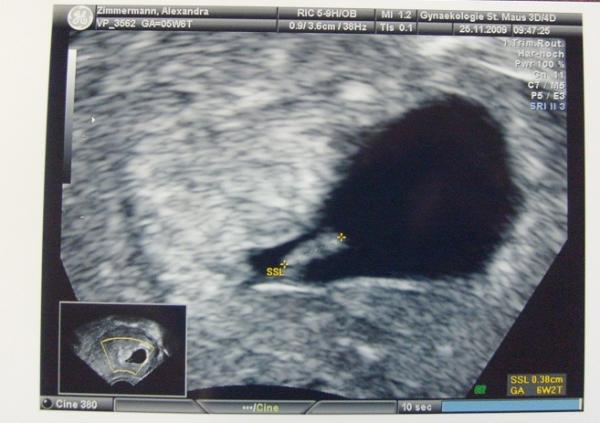

Sooo ich war heute früh einfach mal beim FA! Es ist nur eins und viel weiter bin ich, wenn überhaupt auch nicht, also der PC hat jetzt an hand der Größe 3 Tage drauf gerechnet also, ET bleibt erstmal wie er ist. Herzchen schlägt und alles ist super. Man man *g*

Bild zu Es ist nur eins! - Forum für Juli - Mamis